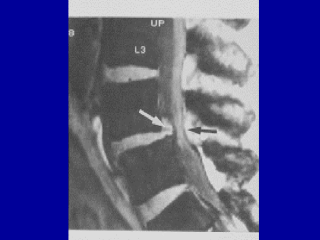

This is another view here. We can see obviously a narrowing of the vertebral canal.